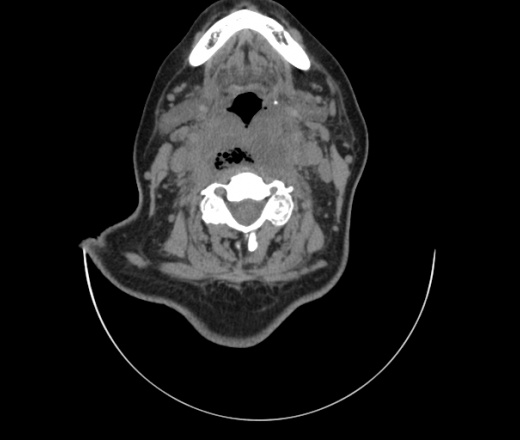

Женщина поступила в х/о спустя 4 дня после того как при употреблении карася подавилась костью.

Наличие газа в средостении на протяжении тел С2-С6 (медиастинальна эмфизема); рыбная кость на уровне тела С6.

При всем уважении, но говорить о медиастинальной эмфиземе, оценивая мягкие ткани шеи, как-то слишком резко. На мой взгляд, это ретрофарингеальное пространство.

Эвакуировали почти 100мл гноя. Но кость не смогли найти. Думаю что она даст дальнейшее ослоднение. Эндоскопически за черпалонадгортаной звязкой не смогли зайти в пищевод, все мягкие ткани отечные, просвет пищевода сдавлен. По всей видимости параэзофагеальная клетчака тоже задействована. Эмпиема, если ее можно так назвать, незнаю как правильно дошла до уровня яремной вырезки. Чем закончиться напишу. Ждем медиастинита.

Флегмона заглоточного пространства шеи, только операция, флегмоны вскрывают. Риск медиастинита.

Согласен с Вами; конечно, наличие газа в клетчатке ретрофарингеального пространства (затмение с опечаткой..). К сожалению, процесс "продвигается" к медиастиниту. Но почему никто, не отмечает наличие рыб. кости; или это для Всех очевидно?

Так вы уже отметили. Хотя ориентировал бы не скелетотопически, а на перстнечерпаловидный сустав.

Кость то мы сразу выявили, размеры где то 17*2мм, но ее так и не получается найти в этой каше